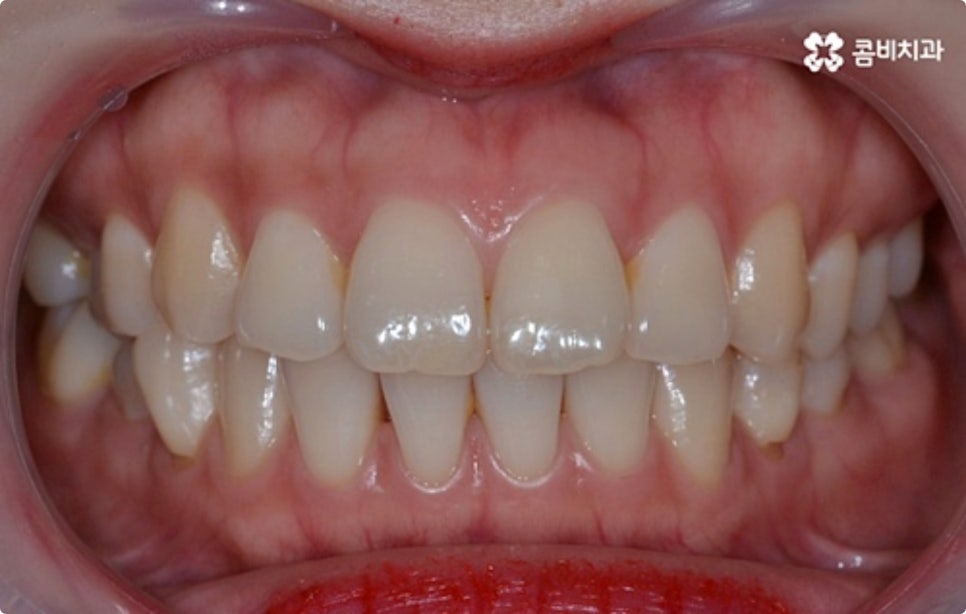

클리피씨 교정도 치아 색상의 세라믹 재질을 사용하기 때문에 심미성이 높은 편이지만 만약에 장치가 아예 겉으로 드러나지 않았으면 좋겠다고 생각하신다면 브라켓을 치아 안쪽에 부착하는 설측교정을 이용할 수 있는데요. 하지만 설측교정은 혀와 맞닿는 부분의 이물감, 통증, 발음상 문제 등을 일으킬 수 있기 때문에 잘 보이는 윗니는 설측으로, 잘 드러나지 않는 아랫니는 보통 교정과 같이 순측 (입술쪽) 으로 진행하는 콤비교정을 통해 이를 보완할 수 있어요. 사진에서 살펴보실 수 있는 케이스 역시 이렇게 콤비로 진행한 직장인치아교정 과정으로 시간이 지날수록 점차 치열이 가지런해지고 교합이 올바르게 개선되는 것을 확인해 보실 수 있습니다.